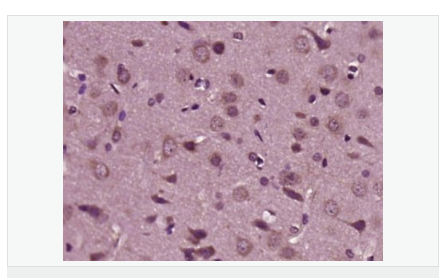

神經(jīng)膠質(zhì)生長因子